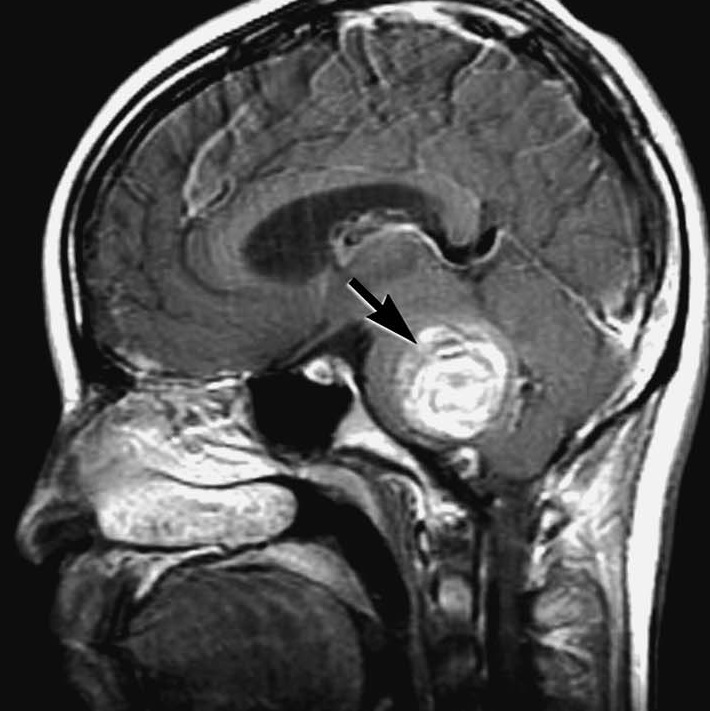

68岁王奶奶一开始诊断出脑海绵状血管瘤还是30年前,那是一开始出血。一开始出血并没有给王奶奶带来太大的伤害,加上血管瘤位置深入脑干,手术不易进入,便选择保守治疗。在与脑海绵状血管瘤和平共处了30年后,王奶奶身体开始出现不适。没精神总想睡觉,反应迟钝,逐渐出现头痛呕吐症状,去医院检查得知竟是血管瘤再次出血导致。在医院进行了一系列治疗后出血慢慢吸收。但是没想到二次出血不是结束,时隔两个月后三次出血,王奶奶陷入昏迷,紧急送医抢救,手术治疗。相关阅读:脑干海绵状血管瘤能治好吗?巴特朗菲教授突破“禁区”案例交流

导致王奶奶脑出血的元凶是“脑海绵状血管瘤”。脑海绵状血管瘤也称海绵状血管畸形,是一种脑部血管畸形,其发生率仅次于脑动静脉畸形,是老年人脑出血的主要病因之一。海绵状血管瘤是一种常染色体显性遗传疾病,也可以由放疗、外伤手术、病毒感染等原因引起。海绵状血管瘤可以发生在颅内的任何部位,根据部位和大小的不同,临床症状也有不同,可以表现为无症状、癫痫发作、头痛、脑出血、运动、感觉、视野、神经及语言功能障碍等局部神经功能缺失表现等。治疗方面,由于海绵状血管瘤是一种良性疾病,治疗决策的确定应考虑治疗措施的利弊和自然病程两者之间的平衡。根据患者的临床表现不同而可以选择保守治疗、显微外科手术治疗及立体定向放射外科治疗等方式。

虽然海绵状血管瘤是一种良性疾病,却王奶奶的血管瘤却位于大脑的重要位置--脑干深部。进入这一重要区域且不损害其结构和功能,手术难度大。脑干周围密布神经,常被称为手术的相对禁区。如果多次破裂出血,就可能引起剧烈头痛、视力下降乃至丧失,甚至晕厥昏迷,危及生命。

脑干是大脑的重要区域,是人体的神经中枢,控制着手、脚、眼、口等的活动,一旦受损就会导致其所支配的躯体相应部位“瘫痪”。如果治疗不及时或术中有所损伤,会对患者的表情、语言功能造成较大影响。如果不是多次出血或者神经功能已经受到损伤,脑干区域很多神经外科医生不选择手术,主要是难度太大。